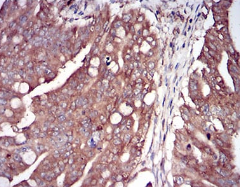

IHC    1/100 - 1/500